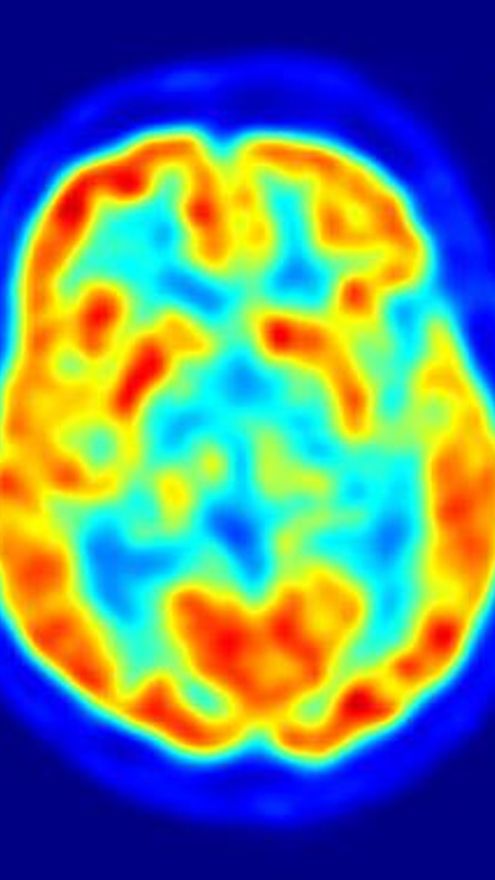

En la esclerosis múltiple, una enfermedad inflamatoria del sistema nervioso central, el daño en los axones mediado por el sistema inmune conduce a defectos neurológicos permanentes. Se desconoce cómo se inicia el daño en los axones. Una visión clásica de la esclerosis múltiple es que la pérdida de la mielina -las cubiertas que aíslan los axones para acelerar la transmisión de señales nerviosas- es un prerrequisito para el daño de los axones.

Los científicos, dirigidos por Martin Kerschensteiner, utilizaron técnicas de imagen en los ratones vivos para identificar una nueva forma de daño en los axones en un modelo experimental de la esclerosis múltiple. Este proceso, llamado 'degeneración axonal focal', consiste en fases secuenciales: el daño localizado en las mitocondrias dentro de los axones, la inflamación de la fibra nerviosa y la fragmentación posterior de los axones.